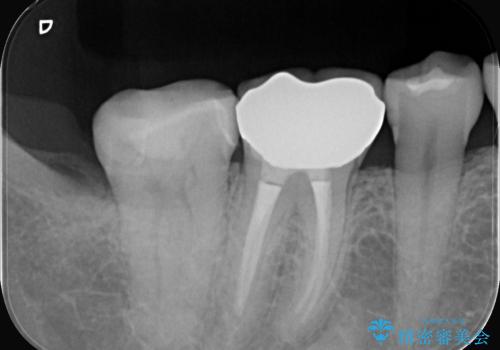

クリーニングにいらした患者さんで、右下7番目の歯の奥側の面や手前の歯との間にう蝕があり、噛む面にも蝕処置によるレジン材料が詰まっていたことから、う蝕も古い材料も全て除去しセラミックインレーでのやり替えとなりました。

右下7近遠心にカリエスを認め、咬合面のCR修復も劣化していたので、カリエスと古い材料を全て除去し新しくCR裏層した後、セラミックインレーをセットしています。セット時はラバーダム防湿を行っています。